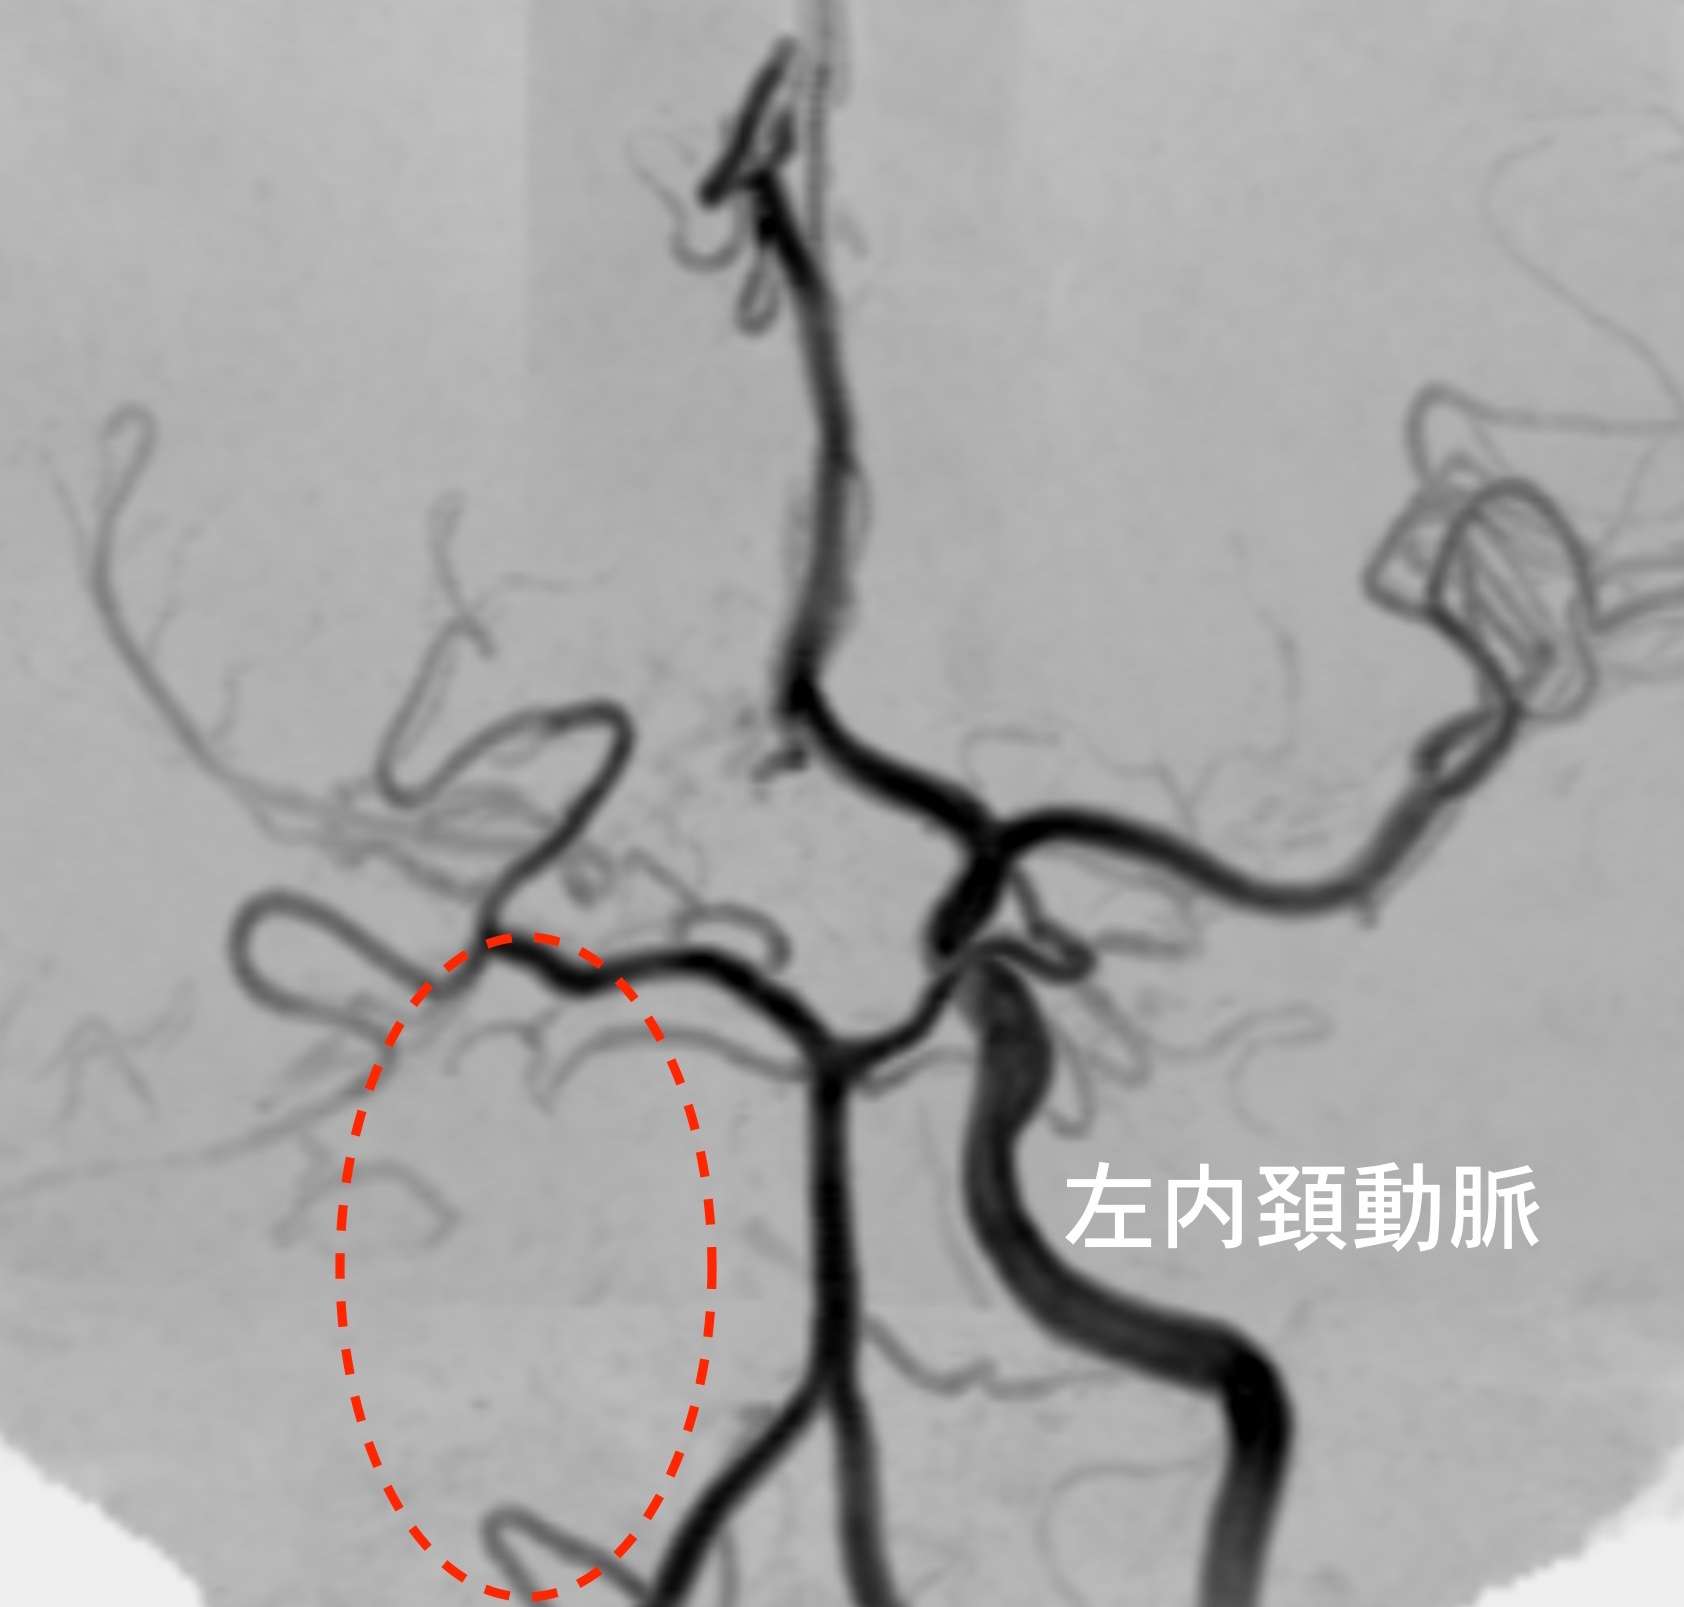

MRI検査で脳の血管を見たところ、

もやもや病と片頭痛

本来ならあるはずの右側の内頚動脈という血管が写っていません。その上の方も血管が全体的に細くなっています。(左内頚動脈は正常です)

※下は他のもやもや病と片頭痛のある方の画像で、左側の内頚動脈が詰まっています。

血管が詰まり血流が悪くなると、それを補おうとして毛細血管が発達してきます。そして、その状態がもやもやと見えるため、「もやもや病」と名付けられました。若い方の脳梗塞や脳出血の原因となります。遺伝子が特定されていますが、必ずしも全員が発病するわけではありません。